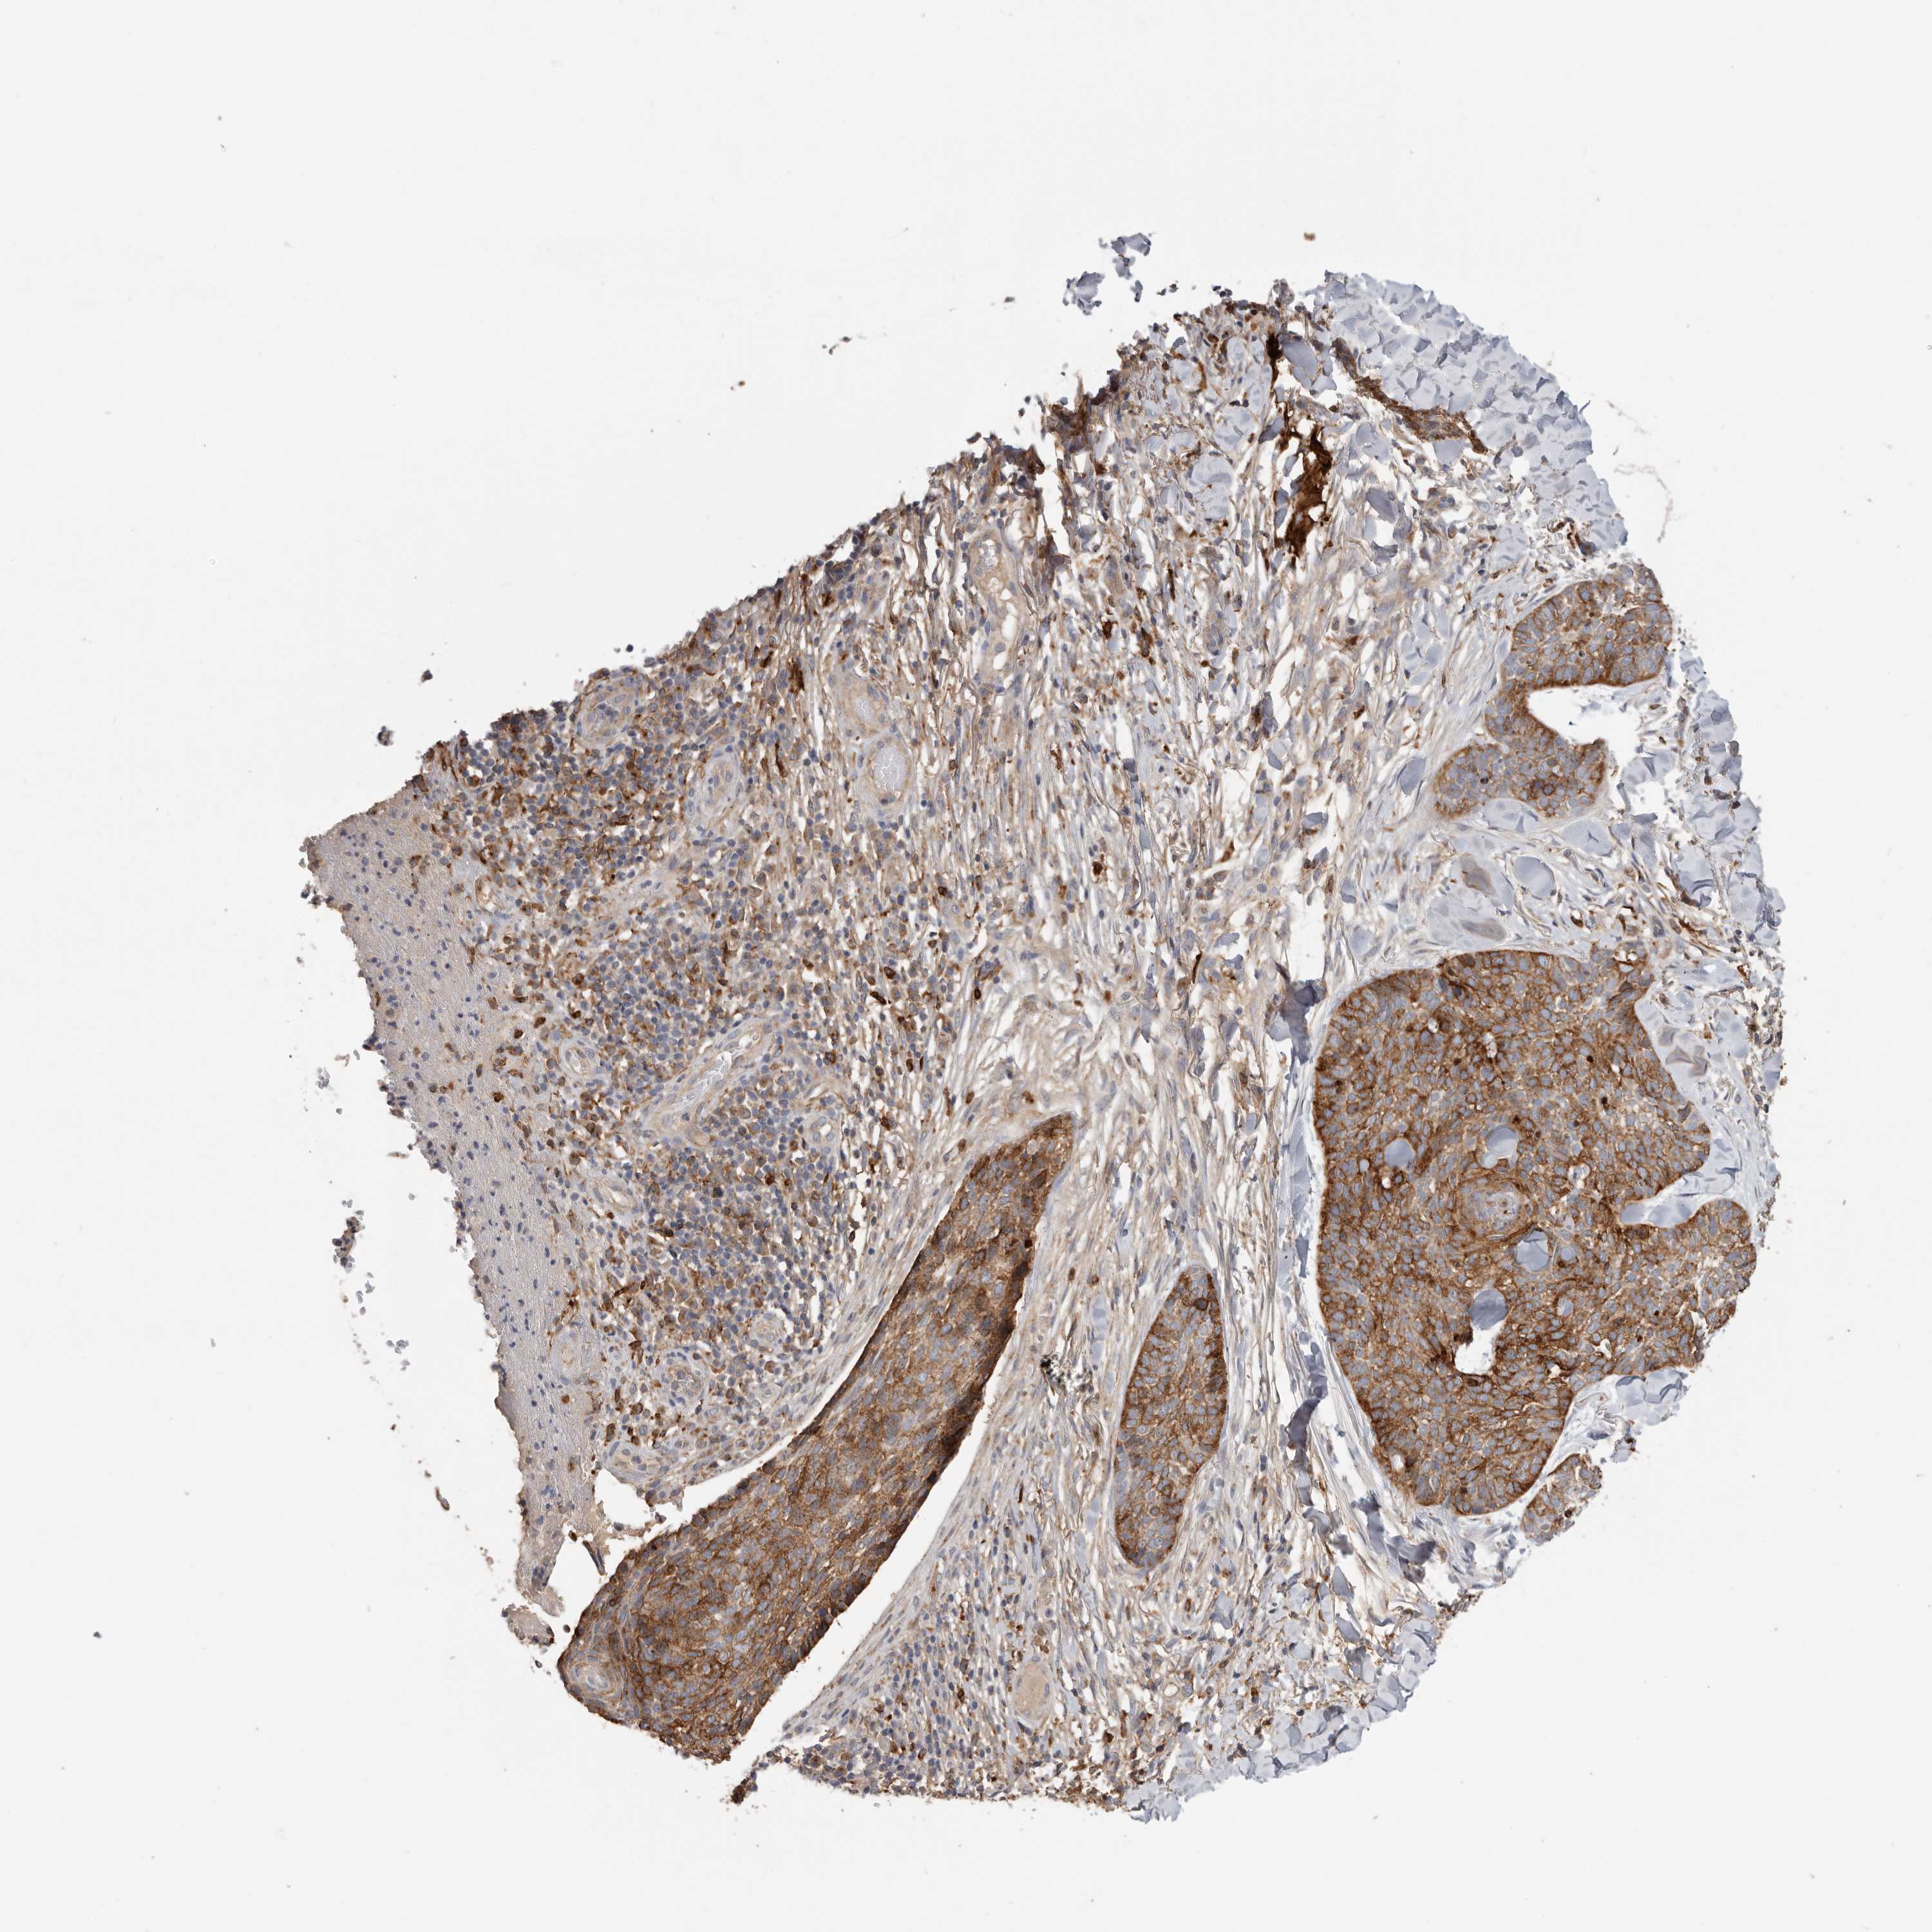

SKIN CANCER - Protein expressioni

A mouse-over function shows sample information and annotation data. Click on an image to view it in a full screen mode. Samples can be filtered based on level of antibody staining by selecting one or several of the following categories: high, medium, low and not detected. The assay and annotation is described here.

Antibody staining in the annotated cell types in the current human tissue is reported as not detected, low, medium, or high, based on conventional immunohistochemistry profiling in selected tissues. This score is based on the combination of the staining intensity and fraction of stained cells.

Each image is clickable and will lead to virtual microscopy that enables deeper exploration of all samples and also displays staining intensity scores, fraction scores and subcellular localization as well as patient and tissue information for each sample.

Antibody HPA028598

Basal cell carcinoma